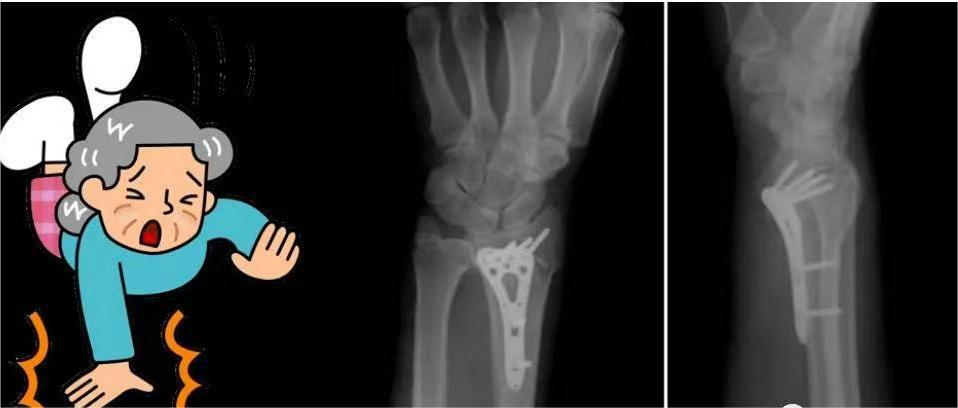

桡骨远端骨折非常常见,多见于老年妇女,骨折发生在桡骨远端2~3cm范围内,常伴桡腕关节及下尺桡关节的损伤。桡骨远端是腕关节的主要构成部分,因此,恢复腕关节功能尤为重要。由于老年人骨质疏松,骨强度下降,因此在跌倒的时候,手腕部着地,极易引发桡骨远端骨折。

虽然桡骨远端骨折一般为轻伤,但如果没有得到及时治疗,也会造成神经血管损伤、关节功能障碍、关节畸形等问题。今天,合卫小编请来了合肥市骨科医院创伤中心二科副主任医师张林胜,给大家讲讲关于桡骨远端骨折的健康知识。